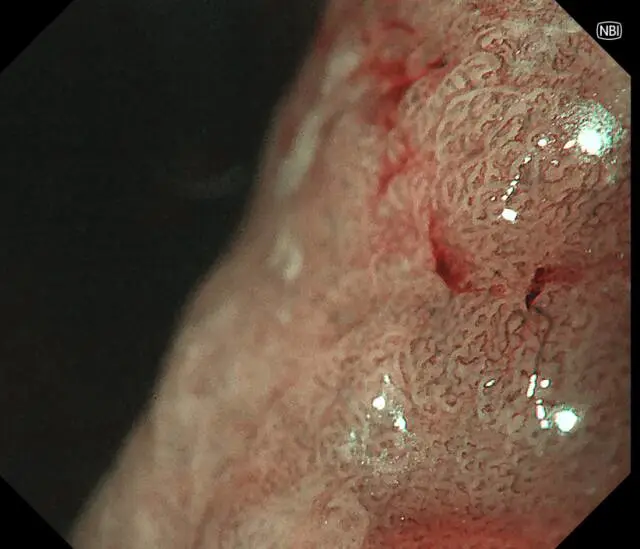

患者王阿姨(化名),65岁。平日里胃肠偶有轻微不适——腹胀,女儿考虑到母亲的年龄,想做个胃早癌筛查,遂带王阿姨来新镜界做胃肠镜精查。

检查中:胃体发现重要异常——胃体巨大息肉,直径约40x40mm!表面充血,带有亚蒂,未来有可能发展为胃癌,健康隐患极大!经与患者家属沟通同意,綦盛麟教授采用ESD(内镜下黏膜剥离术)成功切除巨大息肉。